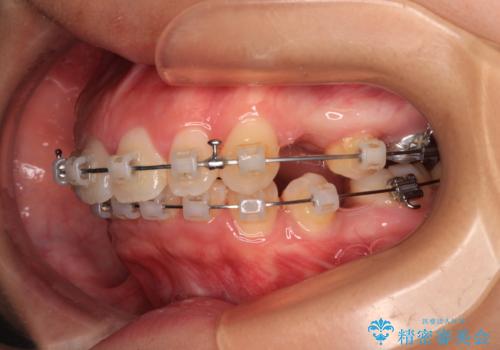

- 矯正装置

- クリアブラケット

- 上顎前歯が飛び出していて唇がうまく閉じられないとのことで来院された患者様です。

くちばしのように前歯が突出していたため、口元を積極的に引っ込めるために、上下左右の小臼歯4本を抜歯することとしました。

また、上顎歯列が下顎に対して前方位に位置していたため、補助装置を用いて上顎歯列を後方に移動させ、より積極的に口元を下げるようにしました。

上下正中位置を改善するため、左下はイレギュラーに第二小臼歯を抜歯しました。そのため治療期間の長期化が予想されましたが、2年半ほどで期待通りの歯列に仕上げることができました。